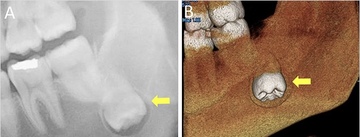

どの歯が親知らず?

歯茎が半分被っている歯、斜めになってる歯

骨の中で逆さまの歯

骨の中で真横の歯

歯を削る道具が、親知らずまで届きにくくて、完全にむし歯を取り切る事ができなかったりします。親知らずの治療はかなり難しいです。一枚目写真の様に真っ直ぐに生えている歯ならば、器具が届けば治療できます。